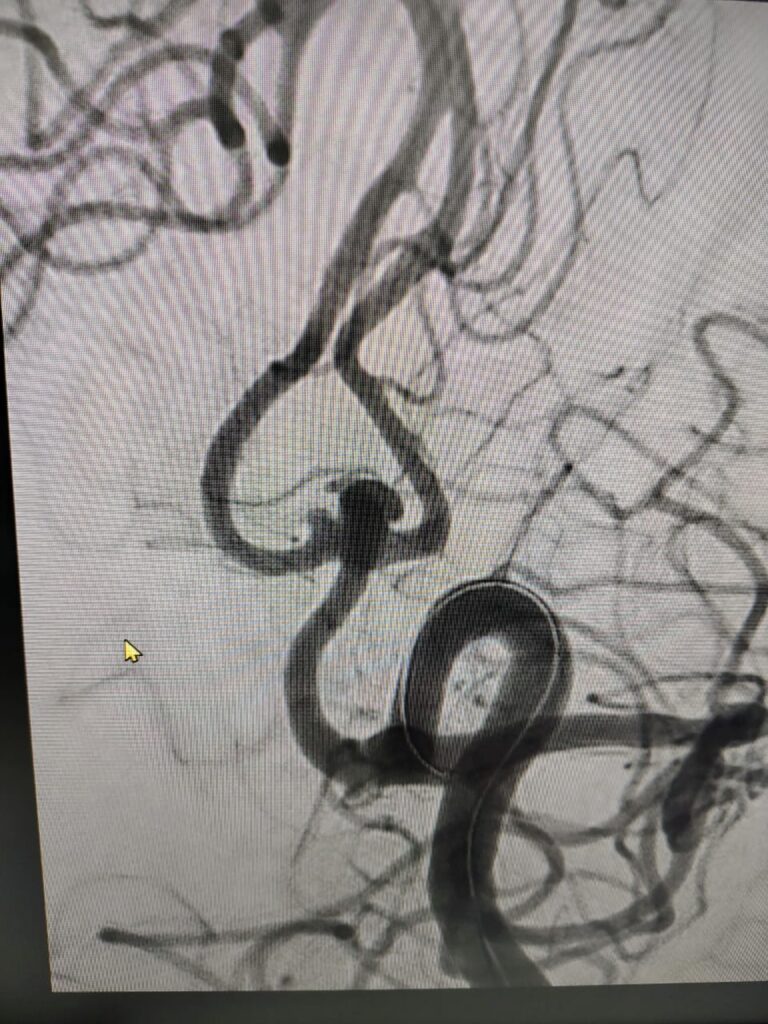

Ruptured Brain aneurysm (left ICA communicating segment wideneck aneurysm) treated with Stent Assisted Coiling.

aneurysm cannulated with microcatheter and microwire

Coiling in live case

after complete coiling and stenting

final result complete coiling and Stenting of brain aneurysm